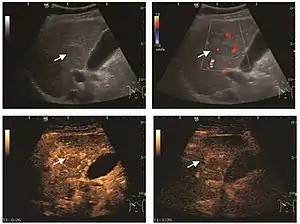

Hemangioma

It is the most common liver tumor with a prevalence of 0.4 – 7.4%. It is generally asymptomatic but also can be associated with pain complaints or cytopenia and/or anemia when it is very bulky. It is unique or paucilocular. It can be associated with other types of benign liver tumors. Characteristic 2D ultrasound appearance is that of a very well defined lesion, with sizes of 2–3 cm or less, showing increased echogenity and, when located in contact with the diaphragm, a "mirror image" phenomenon can be seen. When palpating the liver with the transducer the hemangioma is compressible sending reverberations backwards. Doppler exploration reveals no circulatory signal due to very slow flow speed. CEUS investigation has real diagnosis value due to the typical behavior of progressive CA enhancement of the tumor from the periphery towards the center. The enhancement is slow, during several minutes, depending on the size of hemangioma and on the presence (or absence) of internal thrombosis. During late (sinusoidal) phase, if totally "filled" with CA, hemangioma appears isoechoic to the liver. Deviations from the above described behavior can occur in arterialized hemangiomas or those containing arterio-venous shunts. In these cases, differentiation from a malignant tumor is difficult and requires other imaging procedures, follow up and measurements of the tumor at short time intervals.[4]